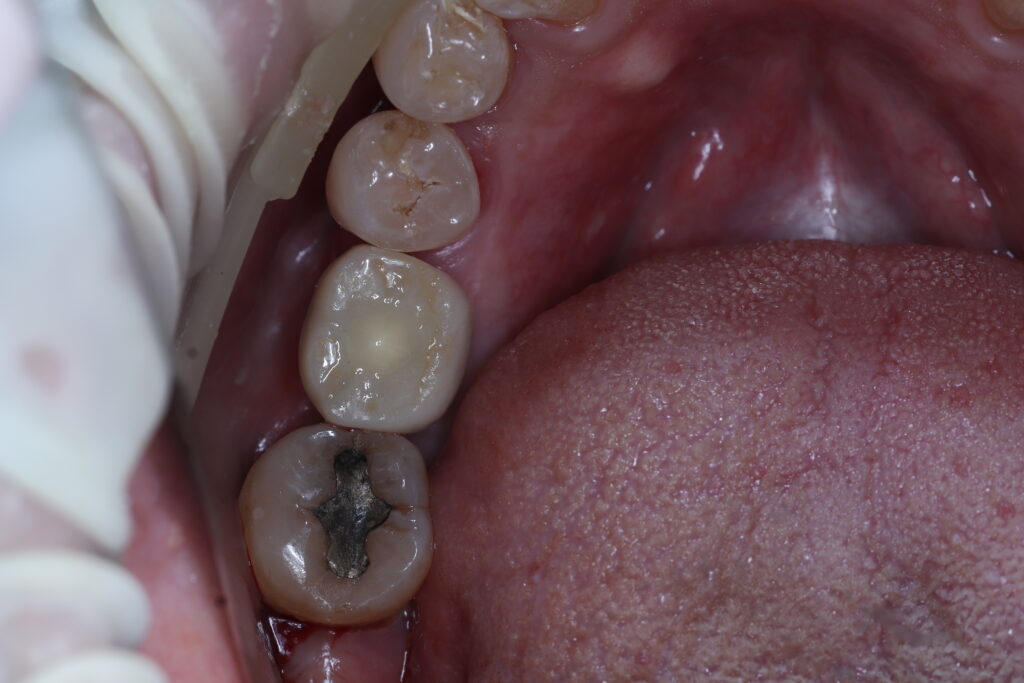

ผลงานบางส่วน ของทีมทันตแพทย์ของคลินิกเรา โดยได้รับอนุญาตให้เผยแพร่ ด้วยความเต็มใจจากผู้ป่วยขอบขอบคุณผู้ป่วยทุกๆท่าน

หลังจากรักษา ใส่ฟันปลอม